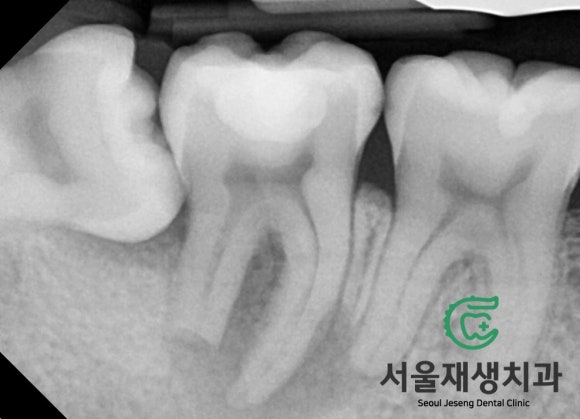

사진 상으로 좌측 아래를 보세요.

사랑니가 옆으로 누워있습니다.

그 앞에 있는 어금니의 뿌리는

칼로 자른 듯 똑! 끊겨있습니다.

뿌리 주위로는 까맣게 뼈가 녹아있구요.